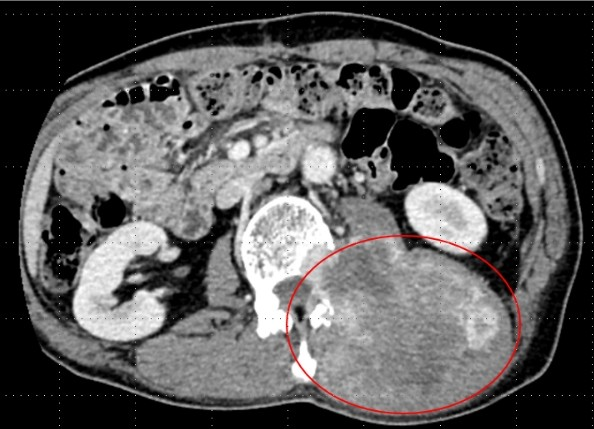

54岁的金先生是浙江台州人 在当地一家工厂上班 两年前,金先生为了改善生活 按揭买了套新房 自此以后每个月背上了房贷 他工作比以前更努力了 加班熬夜是家常便饭 从去年年初开始,金先生时常感觉到腰酸背痛,一开始以为只是上班坐久了,腰肌劳损导致的。直到半年前,他无意中摸到左侧后腰有个肿块,起初还以为是皮下囊肿,可能过几天自己就消下去了。 过了段时间,金先生心中感到不安,他腰痛越来越明显,而且肿块摸上去好像又变大了一点,于是抽空去当地医院就诊。检查后发现,他腰部的肿块大小竟然有10×15厘米,呈纺锤形,如同哈密瓜大小。 病理穿刺检查结果显示为平滑肌肉瘤,这是一种比较罕见的恶性肿瘤,起源于平滑肌细胞,常见于女性子宫、胃肠道、血管壁等部位,但也可能长到身体其他部位。 从影像上看,巨大肿瘤已经侵犯腰椎,而且紧紧贴着腰椎附近的神经和血管。手术难度非常大,当地医院建议金先生赶紧到上级医院治疗。 金先生来到浙江大学医学院附属第二医院骨科,医生介绍,金先生的肿瘤长在左后腰的肌肉里,位置比较深,不易被察觉。等到出现腰痛症状,徒手可以摸出肿块时,肿瘤已经非常大了,还侵犯了腰椎,情况比较复杂。 随后,院方召集了骨科、肿瘤内科、血管外科等多学科专家会诊,制定了详细的治疗方案:平滑肌肉瘤对化疗中度敏感,可以先进行术前的新辅助化疗,尽可能缩小肿瘤范围后,再进行手术切除。 从去年11月底开始,金先生前期做了2次新辅助化疗,一个多月后,肿瘤缩小了一些,为手术切除肿瘤创造了更好的条件。 金先生的手术定在1月14日。为了提高手术安全性,术前,血管外科团队为金先生进行了“腰动脉栓塞术”,以减少术中的出血量。 医生介绍,由于肿瘤巨大,已经侵犯了腰椎,而且紧贴着肠道、肾脏等脏器,附近又分布着下腔静脉、腹主动脉等重要血管和神经,手术时必须非常小心,避免损伤脊髓和重要的血管神经及周围脏器。 先从腹部入路,仔细地把肿瘤分离开来,再从后腰入路,将整个肿瘤“连根拔起”。为了完整切除肿瘤,术中还切除了腰椎1、2、3节的一半椎体。完整切除巨大肿瘤后,金先生的左侧后腰几乎被“掏空”,失去肌肉和软组织的保护,对后续康复会造成影响。 为此,医生用“移花接木”的方法,在保留血供的前提下,将患者右侧背阔肌翻转覆盖到左后腰处,刚好填补了手术留下的缺口,对手术部位起到了很好的保护。 整个手术持续了7个多小时,非常成功。术后一周,金先生就可以下地了。目前,金先生已经出院,进行术后的巩固化疗,以减少复发风险。 医生提醒,平滑肌肉瘤的恶性程度较高,具有侵袭性和转移性,且生长速度较快,可通过血液或淋巴系统扩散到其他器官。早期可能无明显症状,但随着肿瘤增大,可能出现局部肿块、疼痛或压迫周围组织引起相关症状。 因此,如果摸到身上有不明肿块,大家千万不要掉以轻心,应及时到医院进行排查。